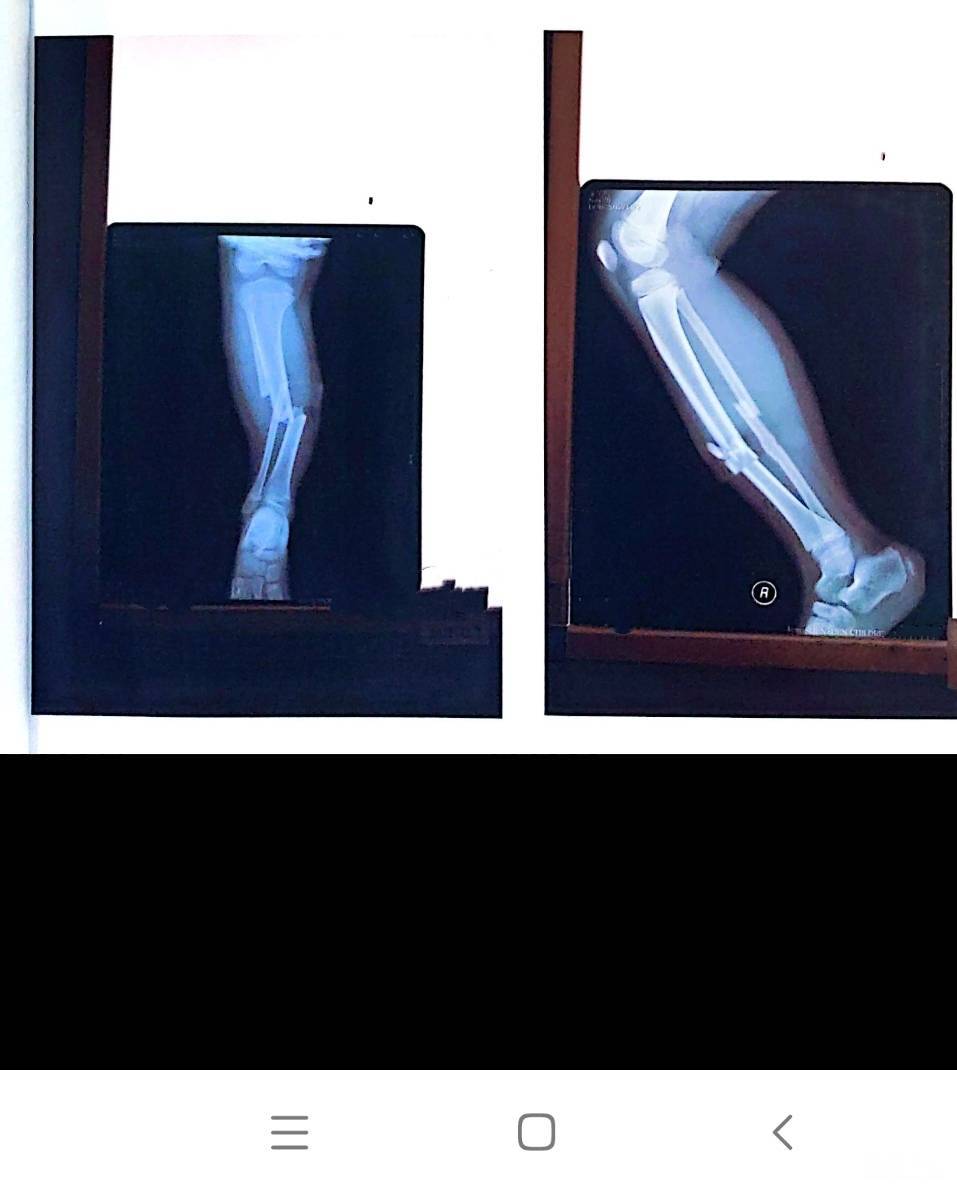

2020年12月31日上午9点40分,龙岗区木棉湾学校在强风天气下仍照常进行学生课间广播体操活动。本次活动前,校方在活动场地置放了一架未固定、无倚靠、并已经折叠好的遮雨棚,棚布随风飞舞。孩子们在无任何教师监护及警示提醒的情况下,愉快地在遮雨棚附近活动。然体操活动进行期间,该遮雨棚因强风作用发生倒塌砸中了学生的右腿,导致他严重的右胫腓骨开放性粉碎骨折。

事故发生至今截止2024年11月,家长经历了长达四年的艰苦医疗救治康复过程后,付出了巨大的时间、心力以及金钱,同时饱受精神折磨。同时受伤学生进行了五次备受煎熬的骨折康复手术,最近一次手术则于2024年4月1日完成。在经历如此艰难痛苦的治疗之后,如今学生才得以勉强正常行走,却遭遇了严峻的骨折后遗症:右腿因骨折后生长异常增加了2.5厘米,导致双下肢不等长,右腿弯曲活动受限,以及由此产生的骨盆倾斜与脊椎侧弯问题。这些并发症使得孩子需要进行长期的复健治疗,它们将深远地影响孩子的未来生活。

2022年12月份深圳市第二人民医院法医临床司法鉴定:根据《人体损伤致残程度分级》最新标准,被评定为两个十级伤残。2024年10月30日广东省深圳市中级人民法院民事判决书(2024)粤03民终***号判决由木棉湾学校承担全部赔偿责任,于法有据。